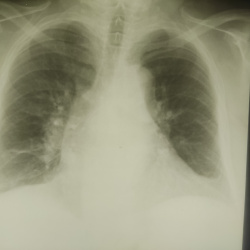

Мужчина, 42 лет, поступил с жалобами на слабость, головную боль, кашель, одышку, считает себя больным в течении 3 дней, когда появились эти жалобы, самостолятельно принимал противовоирусные...